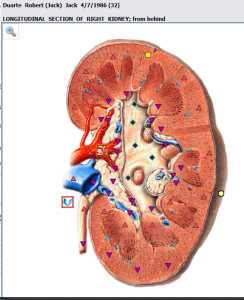

Kidney stones are hard masses that can grow from crystals forming within the kidneys. Doctors call kidney stones “renal calculi,” and the condition of having such stones “nephrolithiasis.”Most kidney stones are made of calcium oxalate. People with a history of kidney stone formation should talk with their doctor to learn what type of stones they have—approximately one stone in three is made of something other than calcium oxalate and one in five contains little if any calcium in any form. Calcium oxalate stone formation is rare in primitive societies, suggesting that this condition is preventable.1People who have formed a calcium oxalate stone are at high risk of forming another kidney stone.